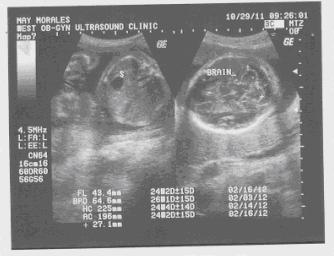

Third Bird Kwentong Kahel

www.biboymorales.com